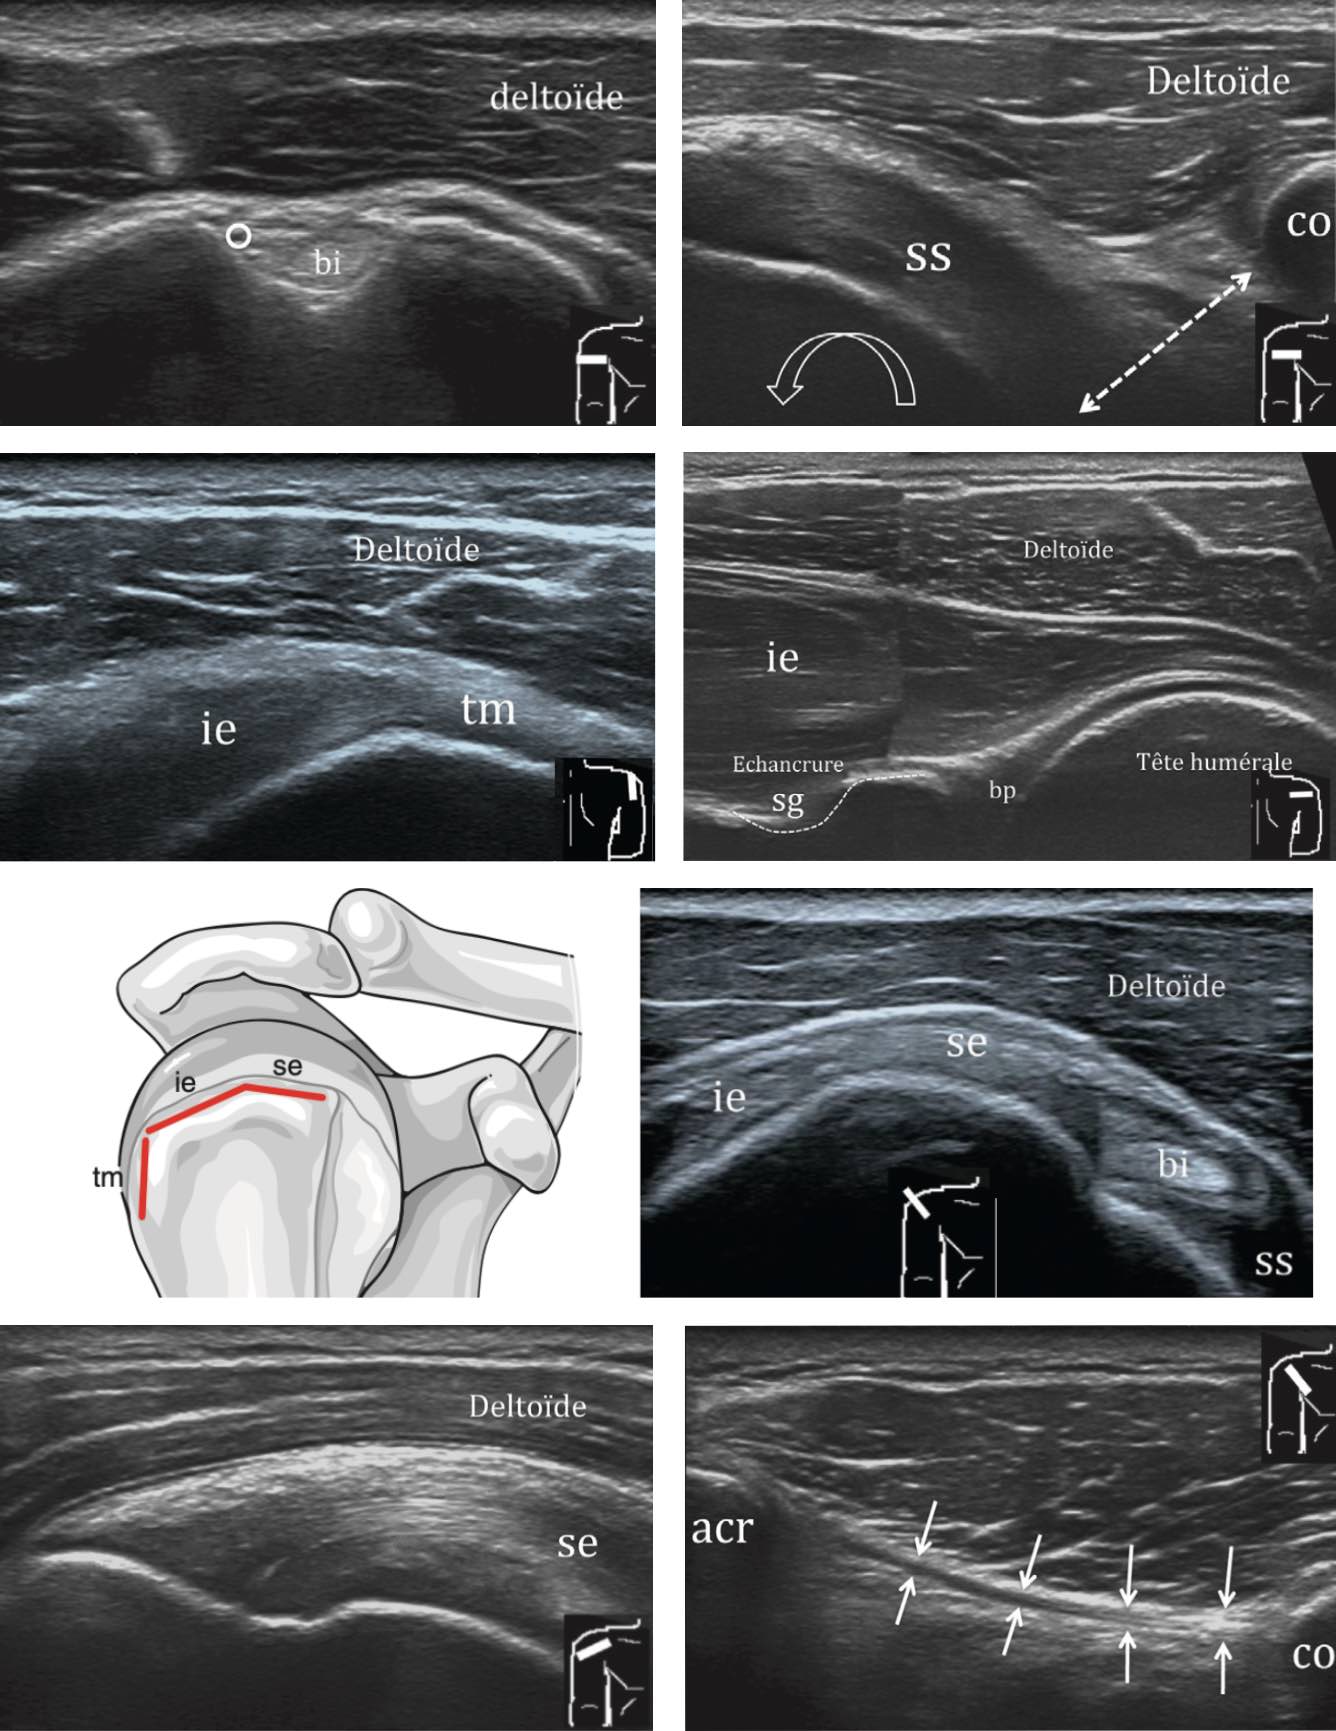

Echographie :

Tendon du long biceps en place, fibrillaire, sans épanchement significatif.

Respect de l'échostructure des tendons des muscles subscapulaire et infraépineux.

Pas d'argument pour un conflit antérieur lors des manœuvres dynamiques.

Pas d'anomalie tendineuse décelable du muscle supra-épineux.

Pas d'épaississement de la bourse sous-acromio-deltoïdienne.

Trophicité conservée des muscles de la coiffe des rotateurs.

Liberté de l'échancrure spino-glénoïdienne.

Arthrose acromio-claviculaire modérée.

Pas d'épanchement gléno-huméral.

espace sous-acromial > 7 mm

espace sous-acromial > 7 mm